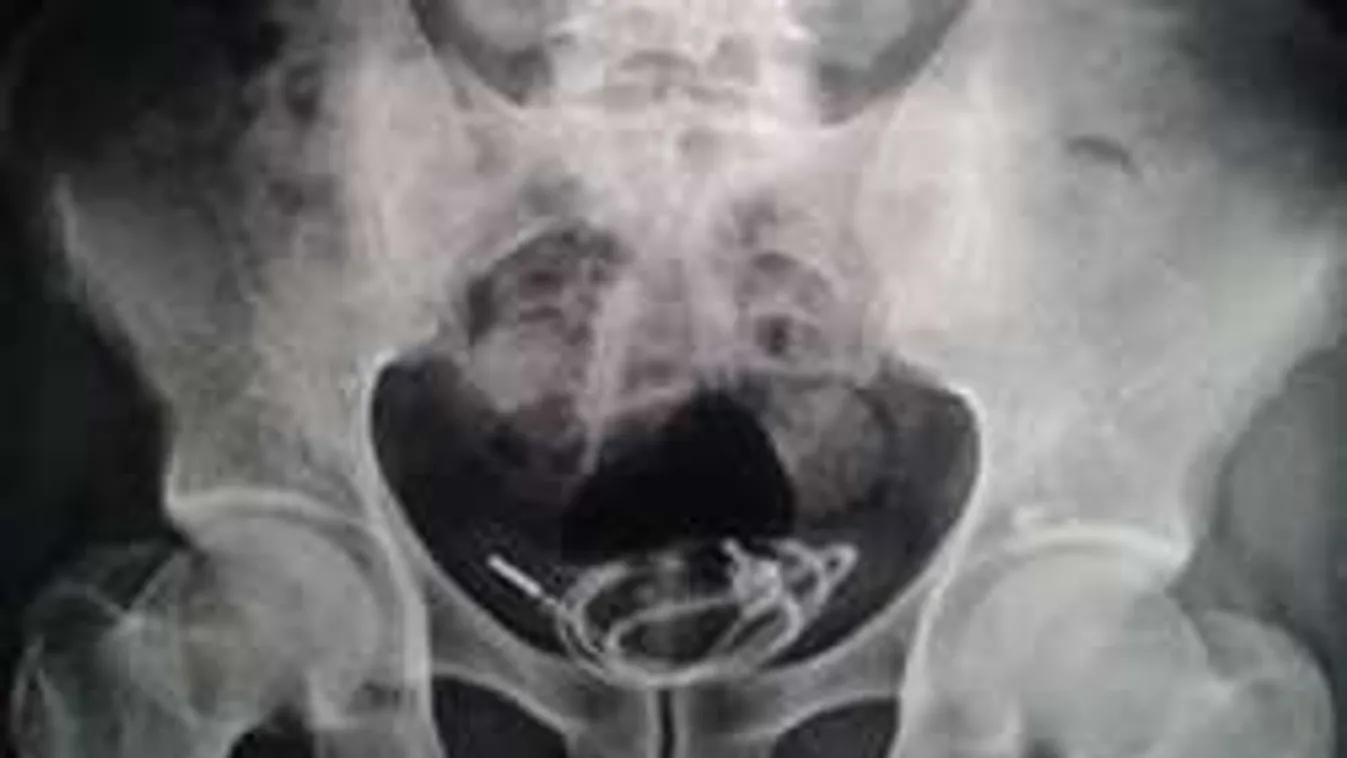

Kábult állapotban feldugta a húgycsövébe a telefonjának töltő zsinórját, hogy egy kicsit feldobja a hajnali maszturbációt.

A manőver befele még sikerült, de ki már nem jött kábel, az ugyanis összecsomózódott a hólyagban. Az sebészek annyira súlyosnak ítélték a helyzetet, hogy egy azonnali mély-altatásos műtét keretében távolították el a húgyhólyagból az oda nem illő idegen testet.

Az egyórás beavatkozás sikerrel zárult, a férfinak végül maradandó károsodása sem lett mérhetetlen hülyeségéből.

A műtétet vezető orvos annyira különlegesnek találta az esetet, hogy „Egy szokatlan tárgy a húgyhólyagban” címmel publikálta is az esetet egy neves sebészeti szaklapban.